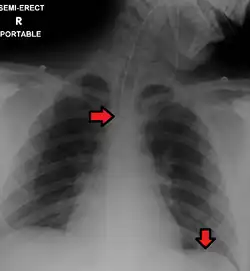

En las vistas anteroposteriores (AP), las posiciones de la fuente y detector de rayos X son revertidas: los rayos X ingresan por el aspecto anterior y egresan por el aspecto posterior del tórax. Las radiografías anteroposteriores del tórax son más difíciles de interpretar que las PA y por ello son generalmente reservadas para situaciones donde es engorroso para el paciente obtener una placa de tórax ordinaria, tales como cuando el paciente no puede levantarse de la cama. En esta situación, equipamiento radiológico móvil es usado para obtener una radiografía de tórax yaciente (conocida como placa supina). Como resultado, la mayoría de las placas supinas son además anteroposteriores (AP).

Placa posteroanterior de tórax en el sujeto normal. -

Placa portátil (o sea, anteroposterior) mostrando tubo endotraqueal y tubo nasogástrico, ambos en correcta posición.